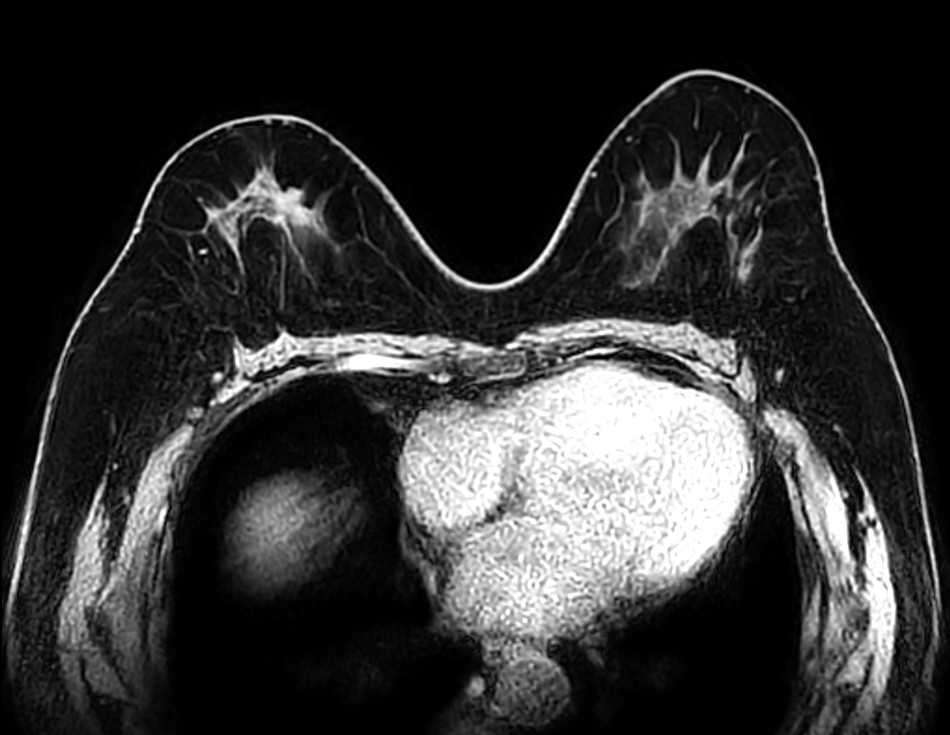

Axial STIR TSE